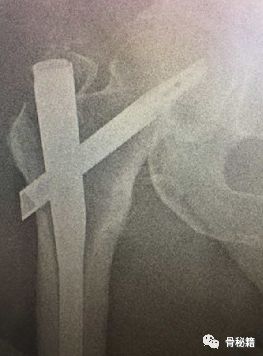

2.将该导针套上一个套筒直达骨皮质,套筒上夹kocher钳,远端连接T把手

3.下面就是复位了,将带螺纹的导针经过T把手向外侧拉,同时向内侧推kocher钳和所夹的套筒。这样一个进一个出,就完成了复位。

4.这种情况下就可以在复位加压的情况下完成骨折的扩髓和固定了